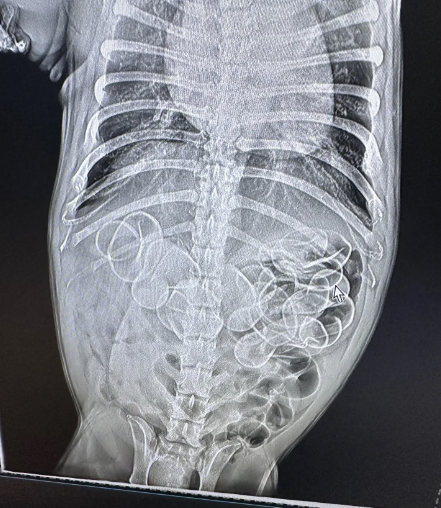

带狗狗去医院一拍片,

肚子里密密麻麻,听取嘎声一片。

医生保守估计有5只,

出于狗身安全考虑建议开腹取出。